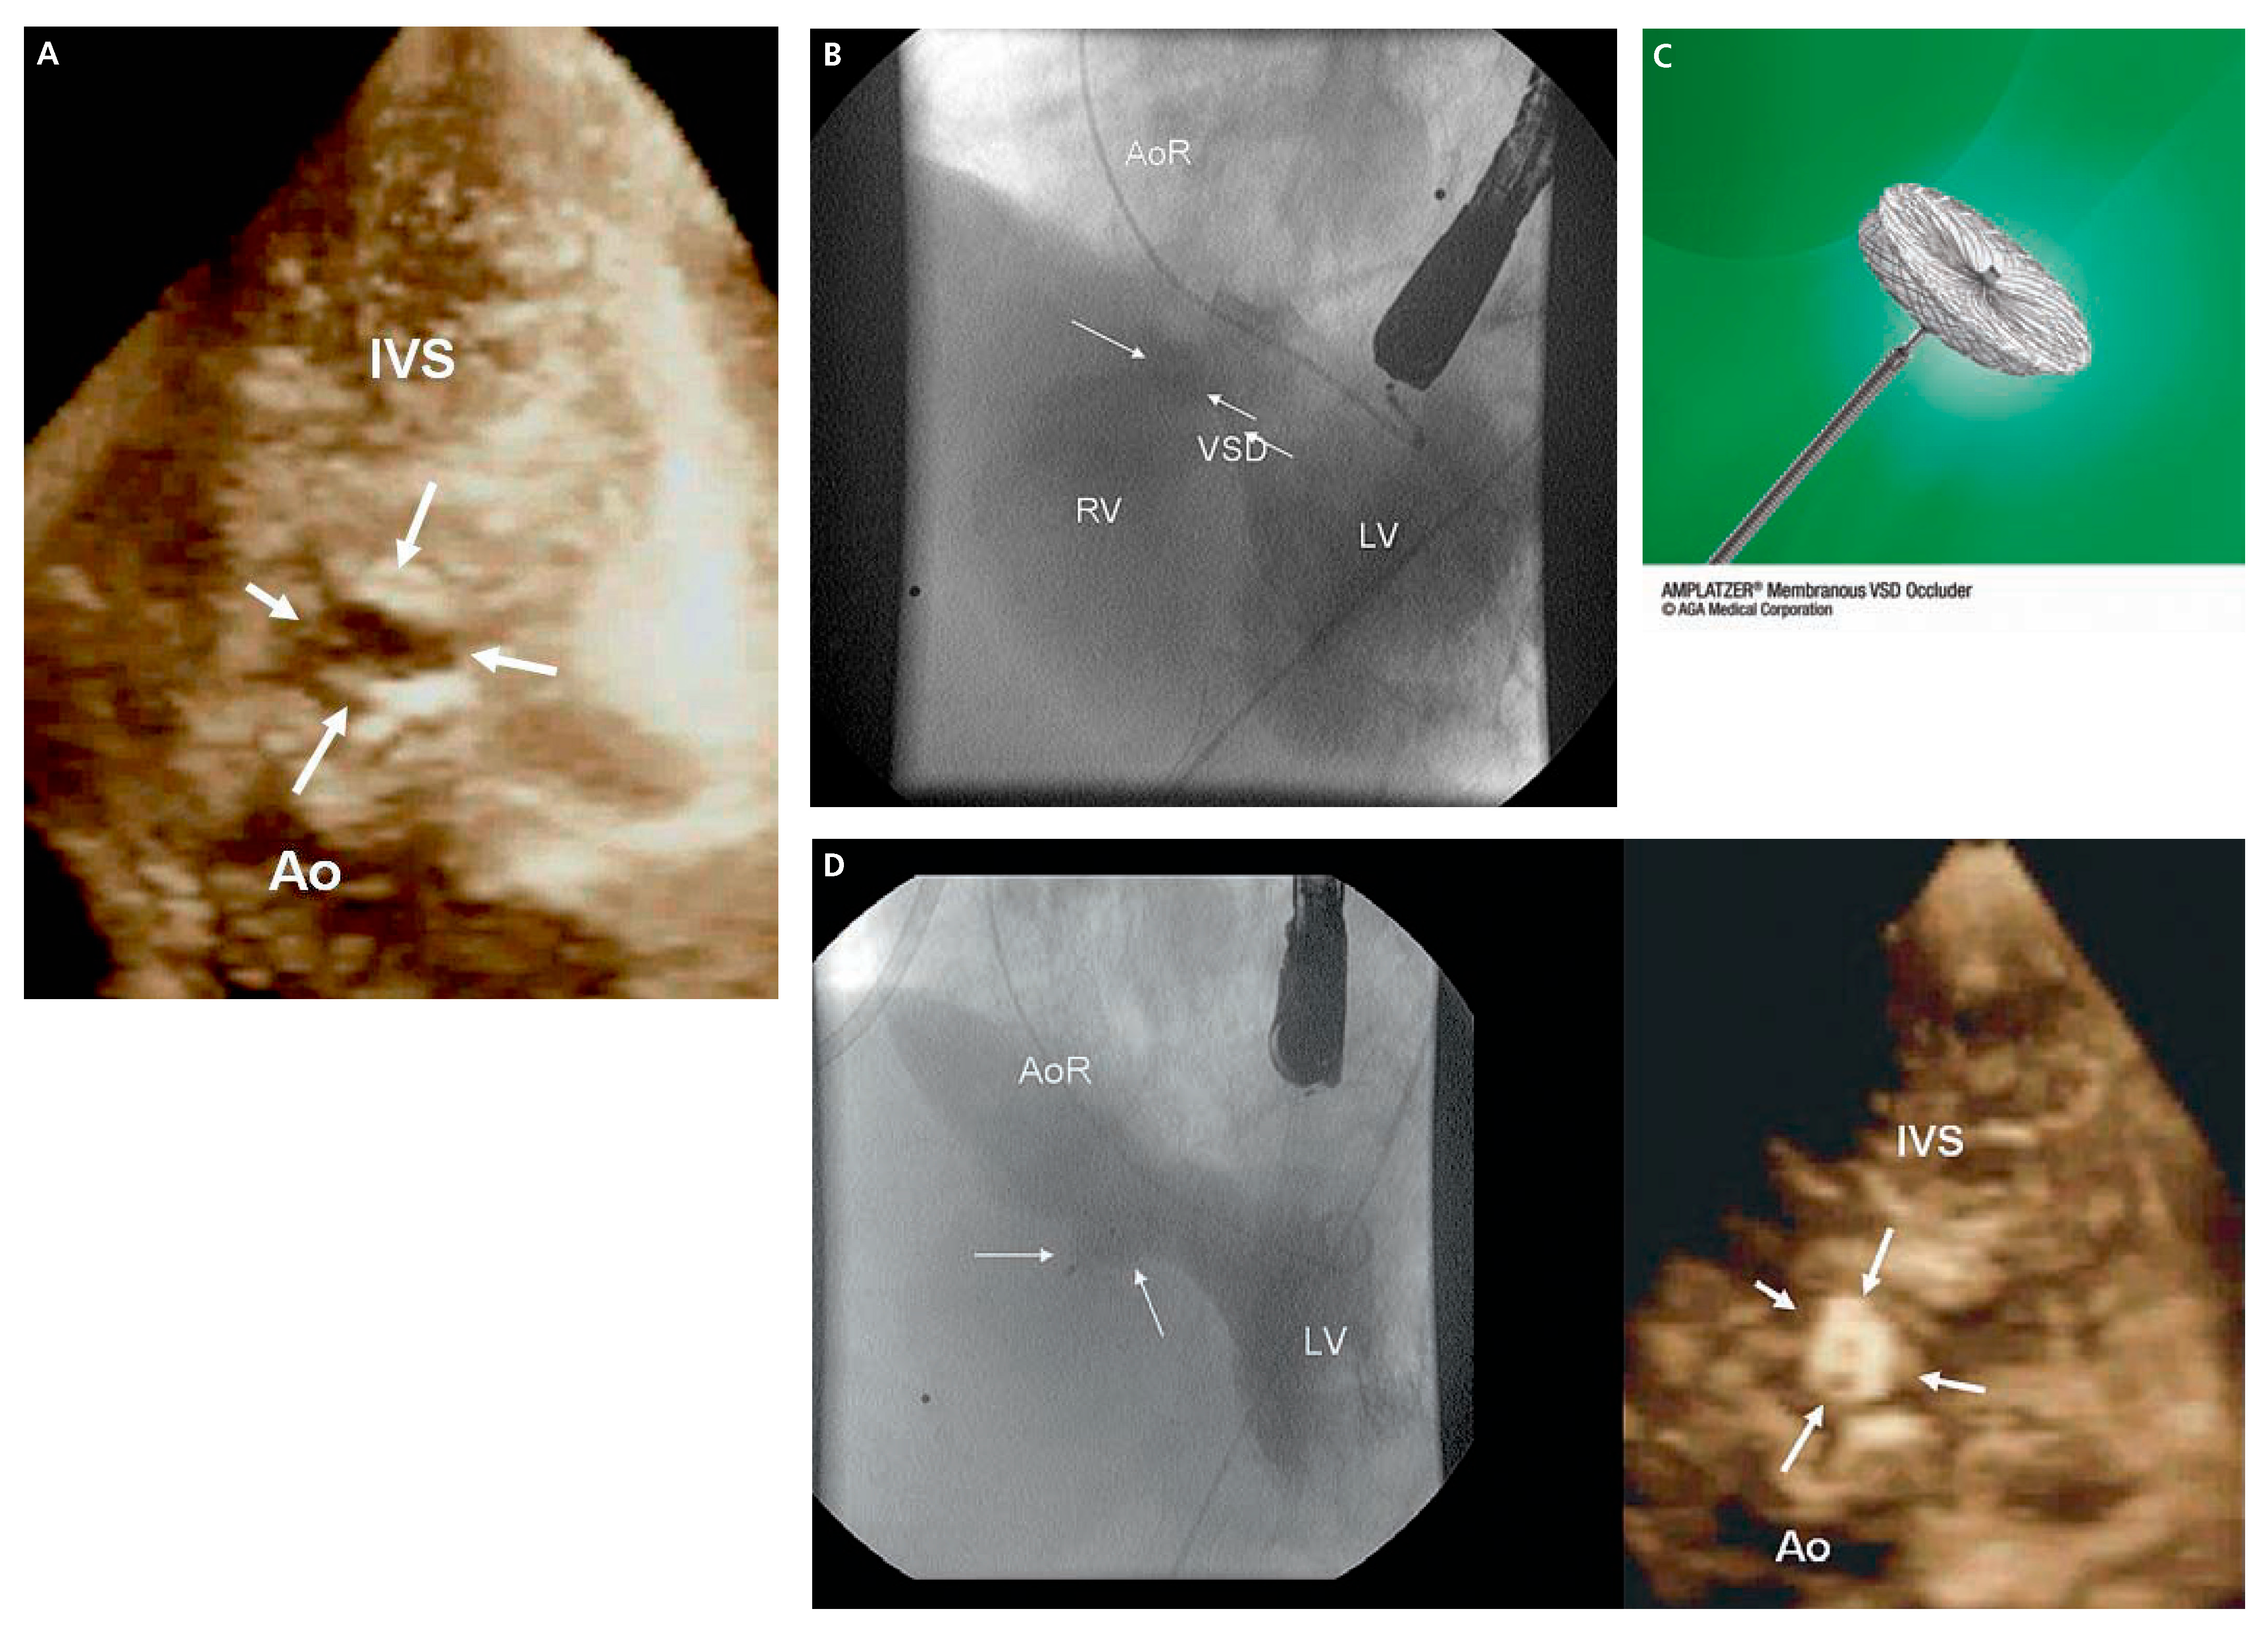

Transcatheter Closure of Perimembranous Ventricular Septal Defect in Adult Using the Amplatzer Septal Occluder: Report of Two Challenging Cases

Case 1

Case 2